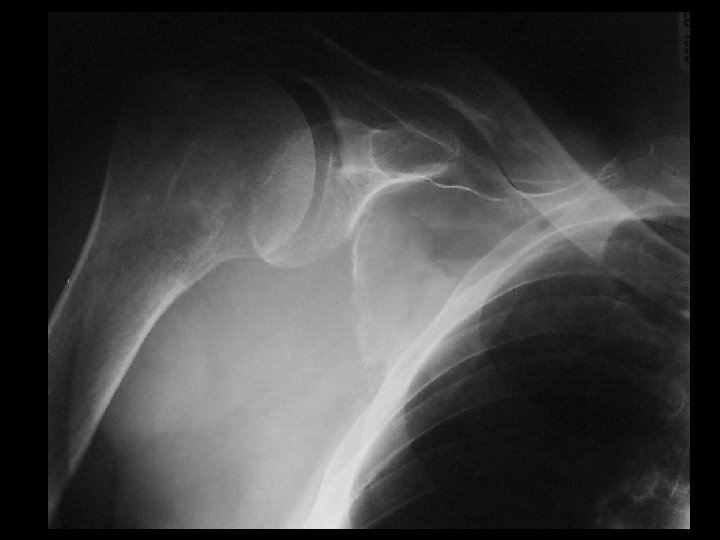

Lymphoma • Findings: – Permeative lesion of the proximal humerus • ddx: – Multiple myeloma – Metastasis – MFH – Infection – Langerhan’s cell histiocytosis